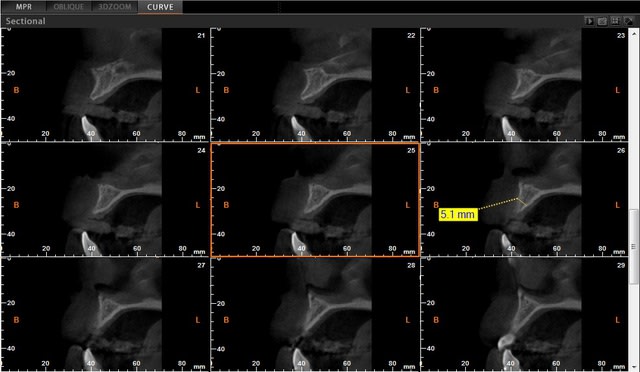

voici les coupes pré et post op. je précise que je fais pas un CBCT aprés chaque greffe. Ici c'est ma deuxieme, et je voulais voir ce que ça donne en post op puis à 5 mois....puisque la fonte des greffons est sujette à polémique bibliographique.....